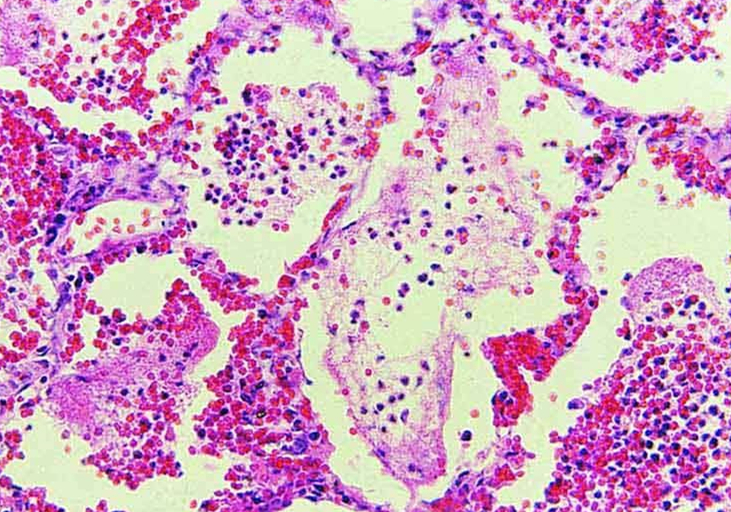

犬布氏杆菌也称为布鲁氏菌,它属于革兰氏阴性小球杆菌,无芽孢及鞭毛,布鲁氏菌为需氧菌,它们对营养的要求很高,最佳生存温度在37.5摄氏度左右。

当狗狗感染布氏杆菌后,这种细菌会侵入狗狗的局部淋巴,并且它们在短时间内会大量繁殖,然后进入血流,侵袭狗狗全身的血液形成菌血症,最后释放内毒素,将毒素散播在狗狗的身体各个部位。